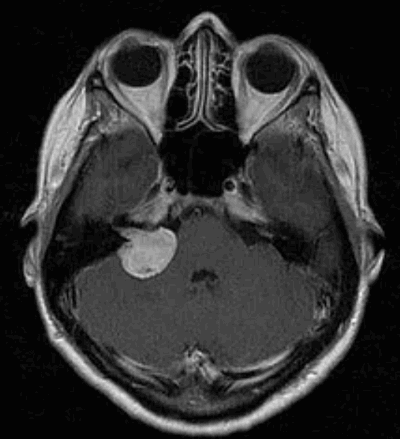

Вестибулярная шваннома (невринома VIII нерва, акустическая невринома) представляет собой доброкачественное новообразование, возникающее из шванновских клеток вестибулярной порции VIII нерва.

Наиболее информативным методом выявления вестибулярных шванном является МРТ головного мозга с контрастным усилением в режиме Т1 и Т2. Это исследование позволяет определить размеры опухоли, наличие перитуморозного отека, наличие признаков окклюзионной гидроцефалии, которая может быть следствием сдавления опухолью IV желудочка. Кроме этого МРТ позволяет провести дифференциальную диагностику с другими опухолями схожей локализации (чаще с менингиомой задней грани пирамиды височной кости). Еще одним стандартом диагностики является КТ в костном режиме. Независимо от снижения слуха стандартом является проведение аппаратной аудиографии.

I стадия: опухоль находится в пределах внутреннего слухового прохода, диаметр экстраканальной части составляет 1-10 мм.

II стадия: опухоль вызывает расширение канала внутреннего слухового прохода, и выходит в мостомозжечковый угол, ее диаметр составляет, 11-20 мм.

III стадия: опухоль распространяется до ствола головного мозга без его компрессии, диаметр составляет 21 - 30 мм.

IV стадия: опухоль вызывает компрессию ствола головного мозга, ее диаметр более 30 мм.